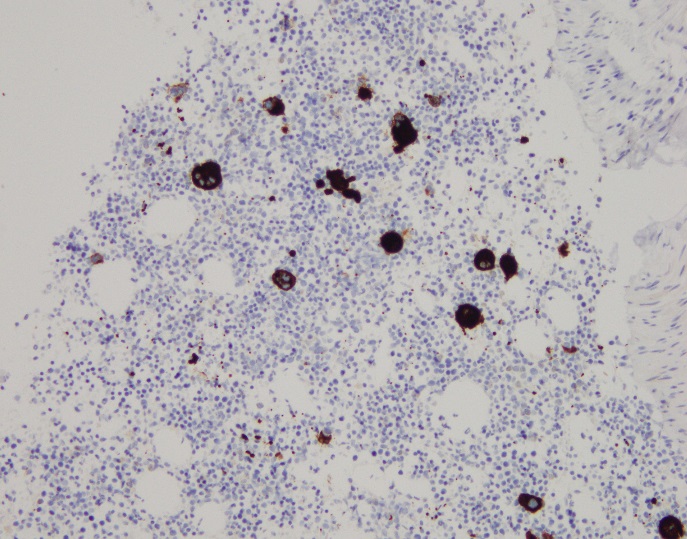

H&E stained sections reveal sheets of large lymphocytes. The lymphoid cells are medium to large in size with irregular nuclear contours and prominent nuclei. Areas of necrosis are prominent. No specific areas of epithelial ulceration are noted. Immunophenotypic characterization of the larger cells reveals positivity for CD20, CD30, CD79a, PAX5, MUM1, Epstein Barr virus encoded RNA (EBER) and a variable Ki-67 proliferation index, which is up to 60-70% in the larger cells, but around 20-30% overall. Only rare cells are positive for BCL-2 and BCL-6. The lymphoma cells are negative for keratin AE1/AE3, CD10, CD4, CD8, CD21, CD23, CD7, CD5, Cyclin D1, CD68, CD56, and CD43. The background T cells express CD5 and CD7 and are a mixture of CD4 and CD8 with CD4 predominance.

The findings are most consistent with EBV-positive DLBCL, NOS (WHO 2017), previously known as EBV positive DLBCL of the elderly (WHO 2008).